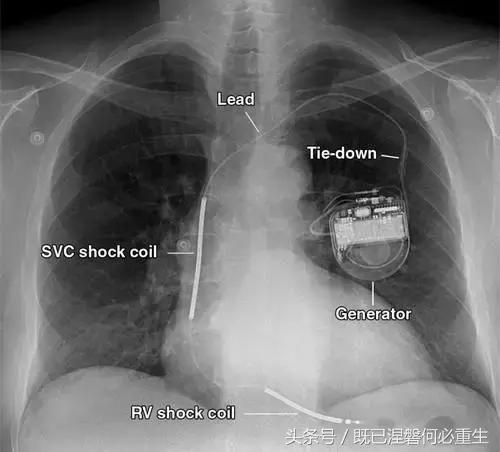

图 1A B 在75岁男性中植入式心律转复除颤器(ICD)的正常部件。

A,额叶胸片显示Medtronic(公司名字)单室ICD。 ICD的基本组件包括发生器,导线和围绕右心室(RV)导线的冲击线圈。 该系统还具有上腔静脉(SVC)中的冲击线圈,其可能不存在于所有系统中。 起搏器没有冲击线圈。 铅固定(见图8A)固定到胸部,并且可能或可能不在胸部X光片上可见。

B,引线通过头连接到发电机(黄色),其保持一个或多个连接端口。 所示系统需要三个端口(一个用于双极起搏或感测元件,一个用于RV休克线圈,一个用于SVC冲击线圈)。 正确放置的引脚将延伸超出连接器(见图9)。 制造商的标志和单个设备标识符的字体被反转,因为发电机被定向以允许在发生器口袋中适当的引线盘绕。 这种定位被设计成减少扭结的风险,这可能导致断裂。 有关制造商徽标的更多信息,请参见图4。